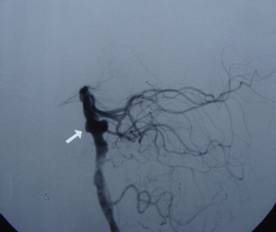

• 我院神经外科成功开展介入手术微创治疗复杂脑动脉瘤

我院神经外科成功开展介入手术微创治疗复杂脑动脉瘤

近期我院神经外科成功开展介入手术微创治疗1例复杂脑动脉瘤,该患者已康复出院。 吴某,56岁,因突发昏迷1小时于2月15日急诊入院。入院时深...